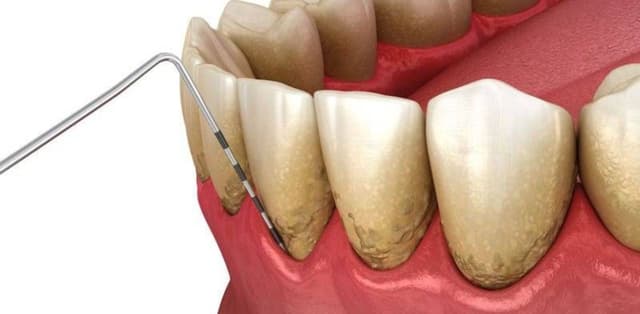

Cao răng là tổ hợp cặn lắng cứng của các muối vô cơ (bao gồm canxi carbonat và phosphate) kết hợp với các cặn lắng mềm (bao gồm mảnh vụn thức ăn, các khoáng chất trong khoang miệng), vi khuẩn, tế bào chết biểu mô, cặn lắng sắt trong huyết thanh. Vị trí bám của […]

Cao răng là tác nhân chính gây ra một số bệnh lý nha khoa nguy hiểm như sâu răng, viêm nha chu, hôi miệng… Bởi vậy, các bác sĩ luôn khuyến cáo mọi người cần thực hiện lấy cao răng thường xuyên tại nha khoa để phòng ngừa bệnh lý. Việc tìm hiểu nguyên nhân […]

Cao răng bám chặt trên răng lâu ngày nếu không được xử lý sẽ dẫn tới những hậu quả vô cùng nguy hiểm đối với sức khỏe răng miệng. Vậy cao răng hình thành như thế nào, làm sao để loại bỏ cao răng? Bài viết sau đây sẽ giải đáp cho bạn những thắc […]